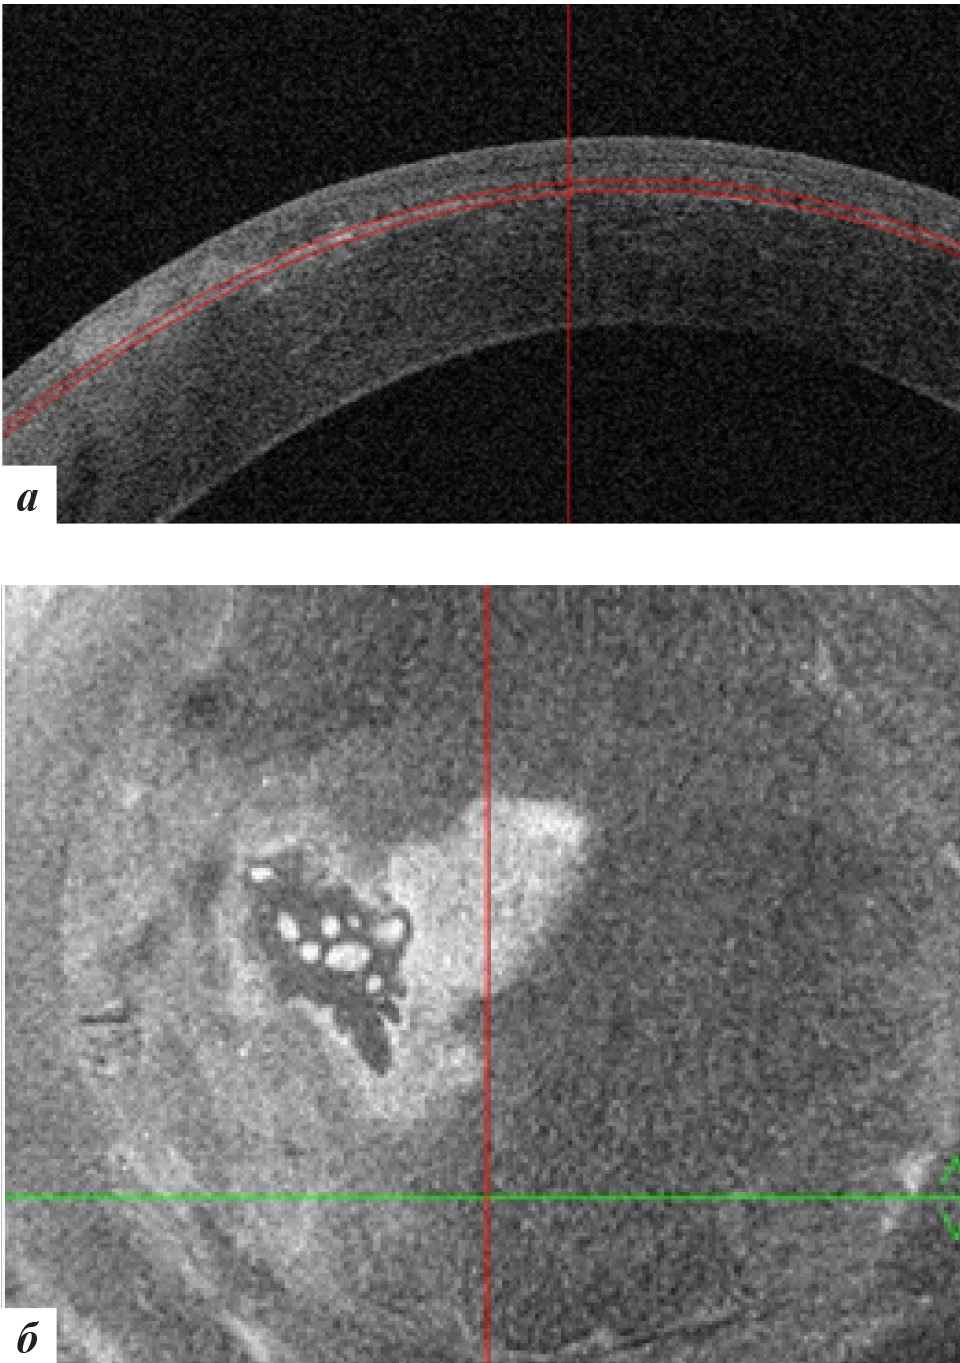

При офтальмобиомикроскопии OS в роговичном интерфейсе в центральной оптической и параоптической зонах отмечалось стойкое облаковидное помутнение при отсутствии рецидива роста эпителиальных клеток (рис. 10), подтвержденное данными ОКТ роговицы (рис. 11).

Рис. 10. Фото роговицы левого глаза через 18 месяцев после лечения

Рис. 11. Данные ОКТ роговицы левого глаза через 18 месяцев после лечения: а – горизонтальная проекция, б – фронтальная проекция